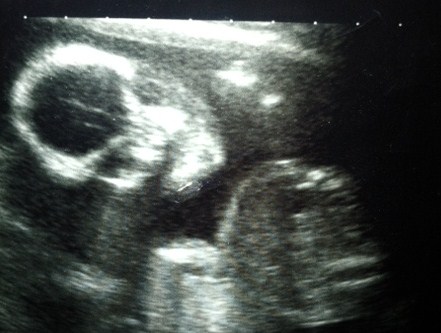

here are two 12 week scan pictures where the nub looks different in both, just for fun i was wondering what gender people thought the little one is based on the skull and nub theories.

xAttachment 3020Attachment 3021